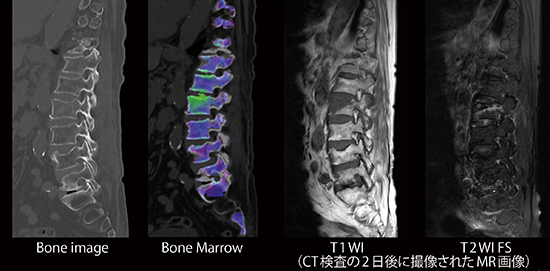

dual energy imagingによる物質弁別の対象は,これまでのヨードや尿酸に加えて,鉄,脂肪,カルシウムなどの検討が進んでいる3),4)。すでに実臨床で有用なツールとして認識されている“DE Bone Marrow”では,カルシウムを抑制(virtual non-calcium)することで,single energyでは描出できなかった骨髄の浮腫性病変を検出することが可能である5),6)。例えば,脊椎の圧迫骨折に関しては,骨折の新旧を鑑別する手法としての有用性が示されており,MRIにおける脂肪抑制画像で見られるような骨髄浮腫の描出が可能である(図2)。外傷患者をすべてMRI firstで精査するには,検査時間やモーションアーチファクトなどの課題もあるため,CTでも同様に骨髄浮腫を描出できることはdual energy imagingの普及を考える上でも有益である。

図2 DE Bone Marrowによる骨折の新旧鑑別

椎体圧迫骨折診断において,新鮮骨折および陳急性骨折が混在している場合には,形態評価のみでは診断,鑑別に苦慮する。受傷日に撮影したDE Bone Marrowでは,受傷2日後のMRI T1WI 低信号,T2WI 高信号領域に一致した部位に浮腫が認められていることがわかる。

(画像ご提供:天草地域医療センター様)